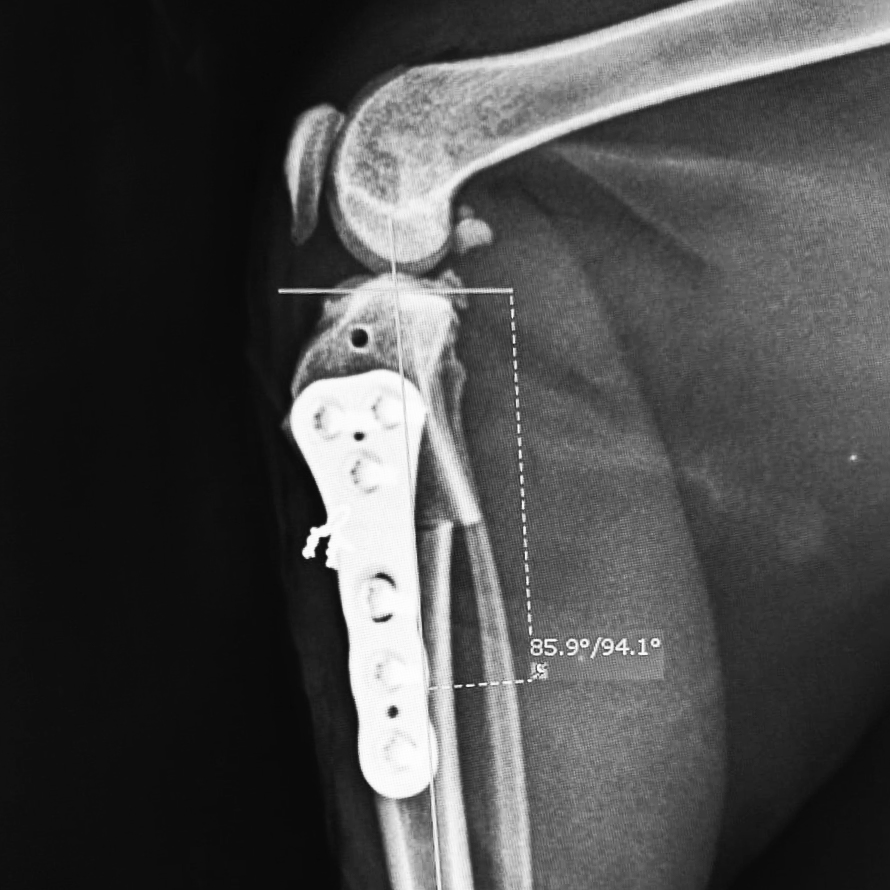

Our CBLO Workshops are designed exclusively for veterinarians seeking to expand their expertise in the Center of Rotation of Angulation-Based Levelling Osteotomy (CBLO) procedure, a surgical technique used to treat cranial cruciate ligament (CCL) rupture in dogs. Our comprehensive program covers stifle anatomy, precise diagnosis of CCL rupture, the correct approach to the stifle joint, thorough stifle examinations, meniscus treatment, the CBLO technique, strategic pre-operative planning, and solutions for potential pitfalls. Combining lectures, demonstrations, and hands-on training with saw bone models and/or cadaveric models, this workshop ensures you acquire practical proficiency under the guidance of experienced surgeons. By the end of the workshop, you will possess a deep understanding of stifle anatomy, the biomechanics of CCL rupture, accurate diagnostic skills, meniscus tear treatment, and the ability to perform CBLO safely and effectively, plan for successful CBLO surgeries, and avoid common pitfalls and complications. Whether you are new to CBLO or seeking to refine your skills, this workshop is ideal for veterinarians dedicated to enhancing their expertise in this area.